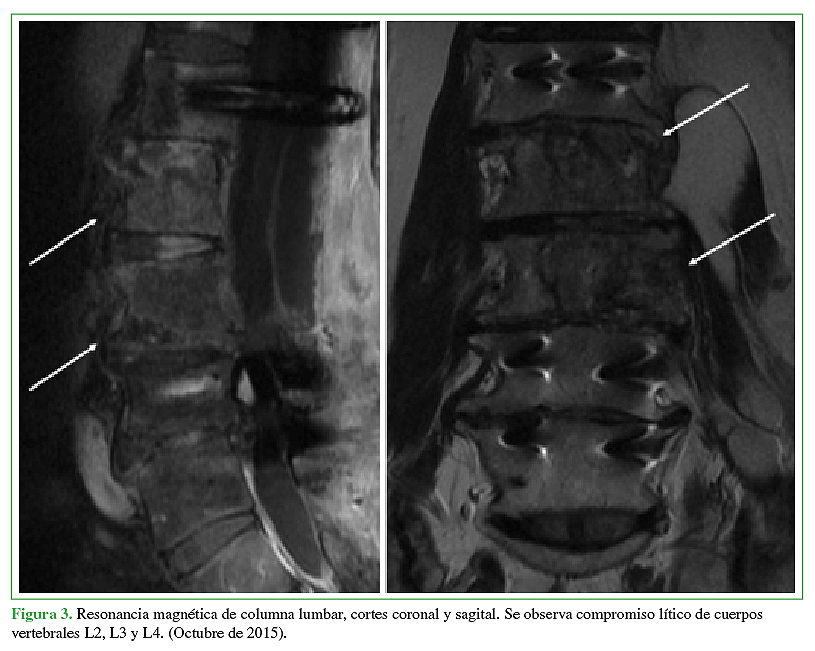

La hidatidosis es una enfermedad causada por el estado larval del platelminto Echinococcus, siendo la especie más prevalente Echinococcus granulosus. Es endémica Eurasia, Africa, Australia y Sudamérica. En Chile tiene una incidencia notificada de 2,1 casos por 100.000 habitantes y a pesar de que está asociada a las zonas ganaderas del sur de Chile, se presenta a lo largo de todo el territorio debido al desplazamiento de la población y su largo período de incubación. Se caracteriza por la presencia de un quiste habitualmente a nivel hepático (75%) o pulmonar (15%). La afectación de otros territorios es menos frecuente y el compromiso óseo es una rareza que no supera el 1 a 2,5%, ya sea en el tejido trabecular o canal medular. El tratamiento por lo general es médico-quirúrgico con resultados clínicos dispares debido a alta tasa de recurrencias y secuelas. La experiencia en el manejo de pacientes afectados con hidatidosis intrarraquídea es limitada debido a su baja frecuencia. Por ello quisimos reportar 2 casos observados en nuestro centro y analizar su manejo.Descargas